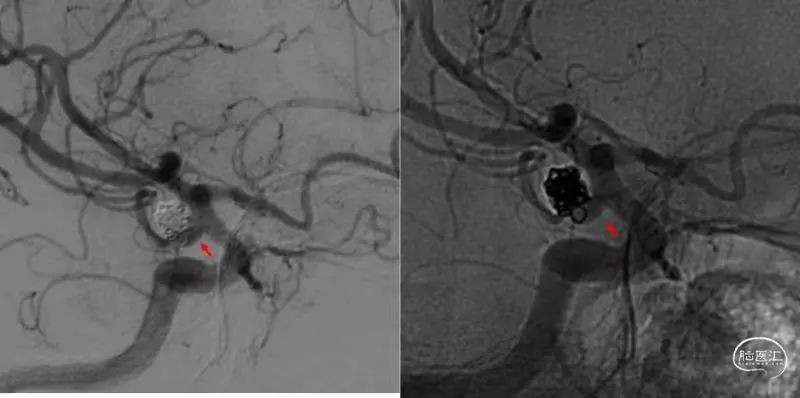

图6

2、Atlas支架在秉承Neuroform系列开环设计的同时,在尾端采用了闭环设计(图7:篮圈部分为闭环设计)。

这一革新的设计使支架导管在通过已释放支架时,减少导管头端与支架内壁的剐蹭,易于导管跟进并通过支架,提高穿网孔技术的成功率。

图7

操作要点及术者体会

有利就有弊,闭环设计虽然提高了再通过率,但却要牺牲一部分贴壁性。尽管支架绝大部分还是开环设计,并不影响支架整体的形态,但尾端的mark点很可能翘离血管壁,与支架导丝“过从甚密”;

当支架导管沿导丝通过支架时,容易与mark点发生纠缠,甚至将部分支架收纳入导管(视频2)。

如未能及时发现,在回撤支架导管时,便可能造成支架的移位。

为避免上述情况的发生,应注意以下几点:

支架的尾端要落在较为平直的血管

完全释放后支架导管多后退一些,确认与近端mark分离

再次通过支架时应注意观察近端mark是否移动

支架释放后,“将导管通过支架,以备不时之需”,不必作为常规操作。